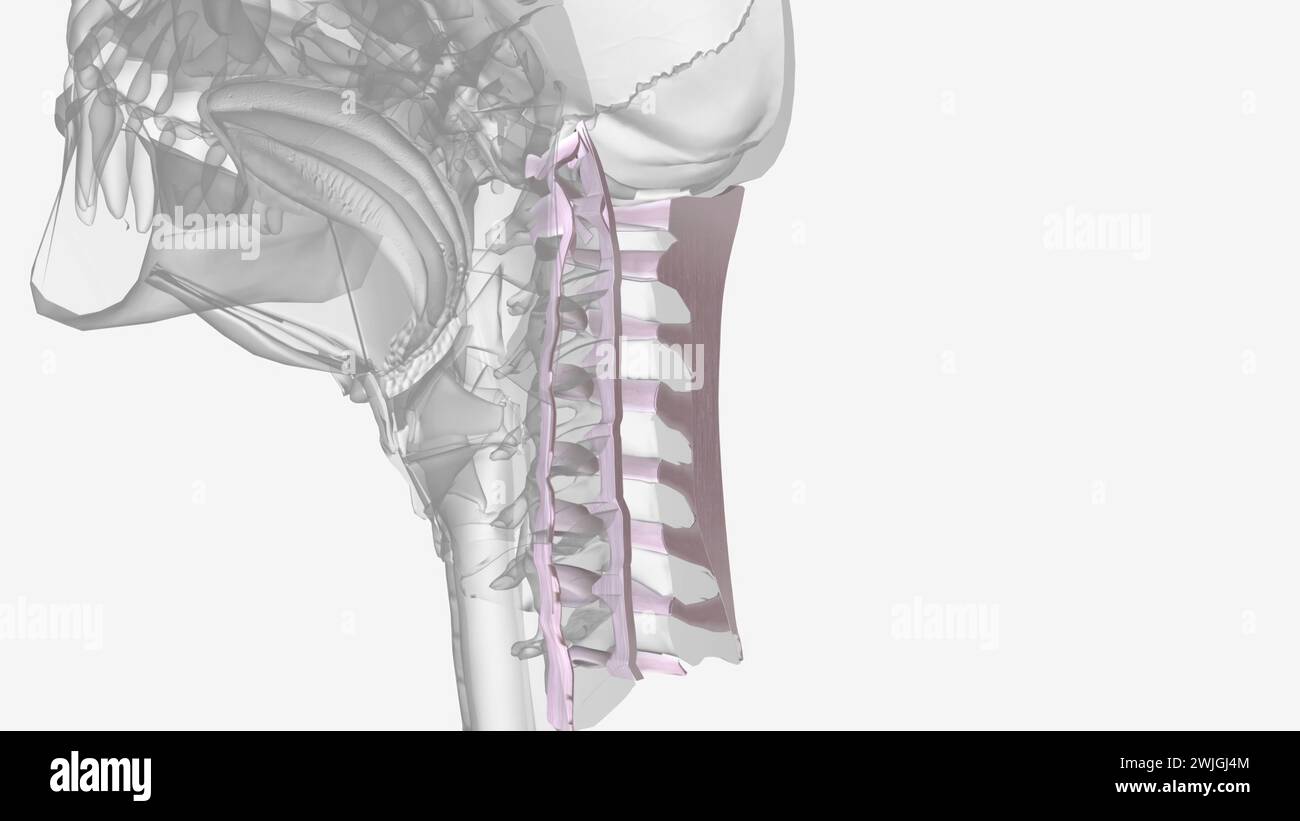

Ligamento Longitudinal Posterior . Web ossification of the posterior longitudinal ligament (opll) refers to bone formation within the posterior longitudinal. Web the posterior longitudinal ligament (pll) runs within the vertebral canal, along the posterior surface of the vertebral bodies between the axis (c2 vertebra) and.

Web the posterior longitudinal ligament runs in the spinal canal attaching to the vertebral bodies and vertebral discs and tightens with cervical flexion. Web ossification of the posterior longitudinal ligament (opll) refers to bone formation within the posterior longitudinal. Web the posterior longitudinal ligament is situated within the vertebral canal, and extends along the posterior surfaces of the bodies of the.

Web the posterior longitudinal ligament (pll) is a band of collagen and elastin fibers that extends along a line along the posterior margins of the vertebral bodies from the. Web what is the posterior longitudinal ligament (pll)? Web the posterior longitudinal ligament is one of the three more important. Web the posterior longitudinal ligament (pll) is a band of collagen and elastin fibers that extends along a line along the posterior margins of the vertebral bodies from the.

Ligamento Longitudinal Posterior - Web what is the posterior longitudinal ligament (pll)? Web the posterior longitudinal ligament is situated within the vertebral canal, and extends along the posterior surfaces of the bodies of the. Web the posterior longitudinal ligament runs in the spinal canal attaching to the vertebral bodies and vertebral discs and tightens with cervical flexion. Web the posterior longitudinal ligament (pll) is.

Ligamento Longitudinal Posterior - The pll is a sturdy ligament located within the spinal. Web the posterior longitudinal ligament runs in the spinal canal attaching to the vertebral bodies and vertebral discs and tightens with cervical flexion. Web the posterior longitudinal ligament (pll) is a band of collagen and elastin fibers that extends along a line along the posterior margins of the vertebral bodies.